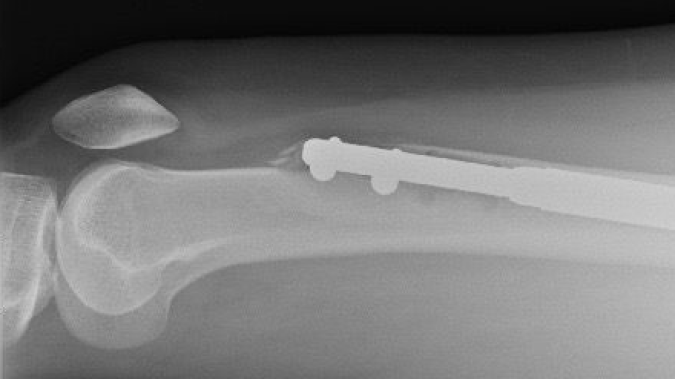

Con este procedimiento, sentir cierto dolor es esperable. Durante la operación, los huesos de las piernas se rompen en dos y una varilla de metal se posiciona adentro.

Las varillas de metal se van expandiendo gradualmente para aumentar su longitud y separar las dos mitades del hueso. El objetivo del procedimiento es aumentar la estatura del paciente. Los huesos rotos deberían volver a unirse gradualmente y llenar así el espacio que se creó entre ellos.

El clavo de la pierna izquierda le había atravesado el fémur, el hueso más fuerte del cuerpo humano. Estaba angustiada, pero dice que el doctor Guichet la calmó.

Seis semanas después, tomografías de la pierna derecha mostraron una alarmante ausencia de crecimiento óseo. Su fémur era básicamente dos pedazos de hueso unidos por una varilla de metal.